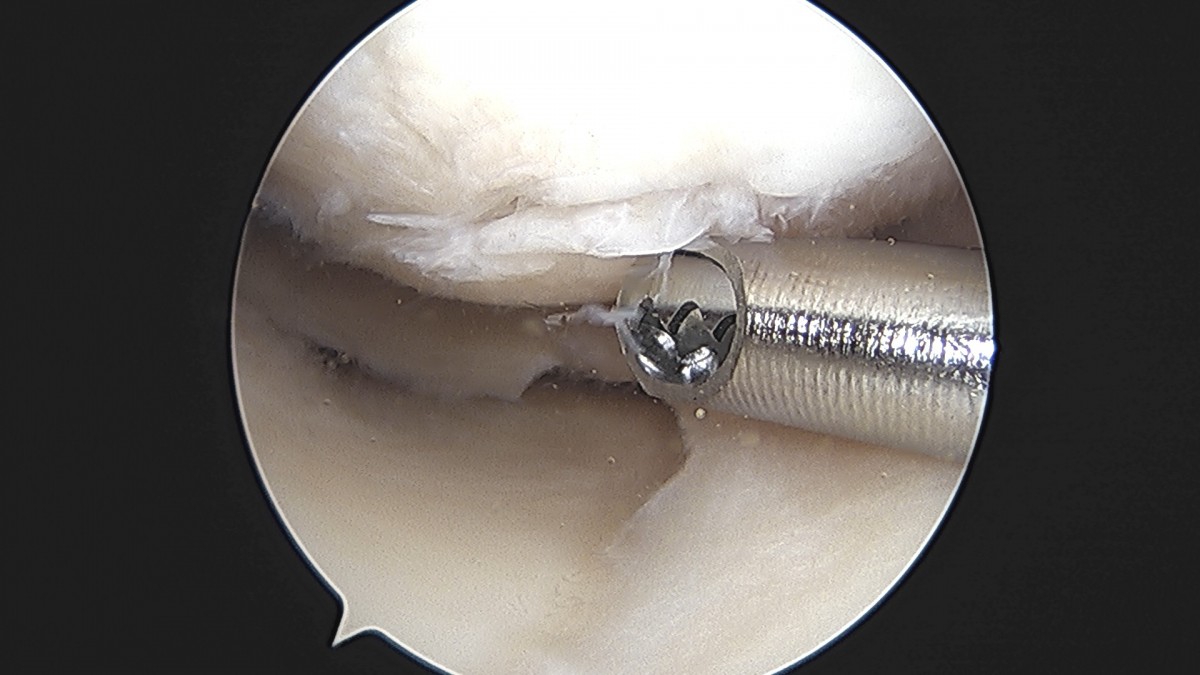

이재상원장님 무릎 반월상 연골판 절제술 박강O 환자

작성자 최고관리자 댓글 0건 조회 381회 작성일 25-09-16 15:47